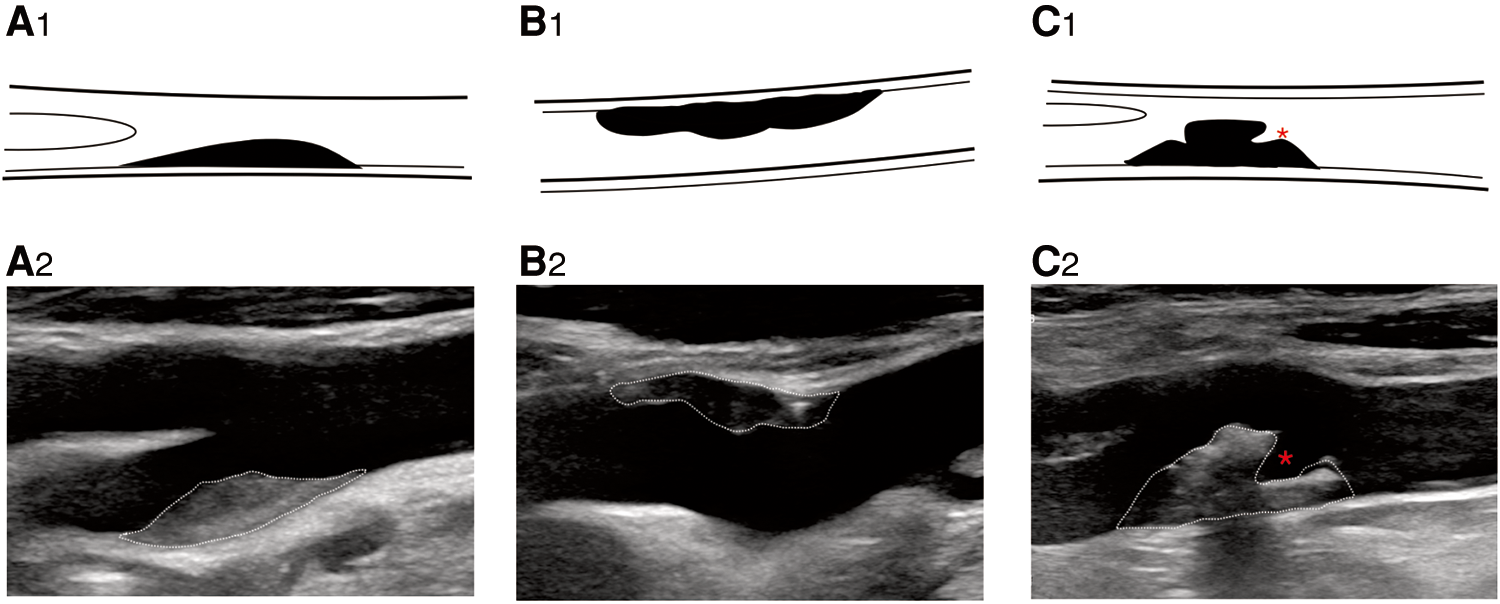

Figure 2

B-mode ultrasound image shows plaque morphology. B-mode ultrasound image shows plaque morphology. (A2) Regular plaque, (B2) irregular plaque, and (C2) ulcerative plaque. * represents plaque ulcer location. (A1–C1) Corresponding schematic diagram.